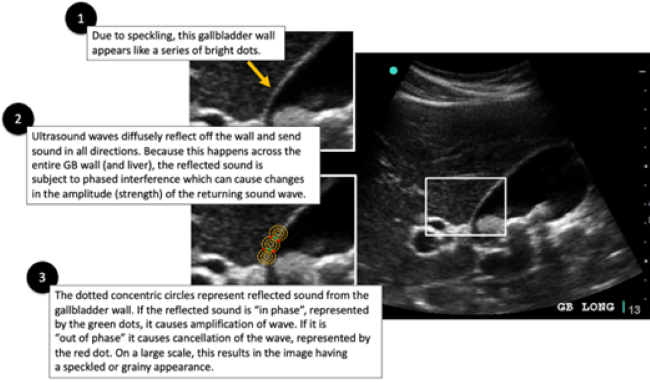

Lipliner_Fig2.pngFigure 2. Image Adaptive Artifact

The result of using speckle reduction algorithms leads to ultrasound images appearing “smoother” with better demarcation of tissue borders. However, speckle reduction comes at a price with the introduction of a new artifact: image adaptive artifact. See Figure 2. Image adaptive artifact allows better border demarcation by increasing contrast between adjacent tissues. Image adaptive artifact is what is observed in the case series by Parker et. al. and called the “lipliner sign.” While reducing or turning off the appropriate feature that causes this image adaptive artifact to occur, the trade-off is that images will become very speckled and grainy. In essence, there is a choice to be made between these two different artifacts, the image adaptive artifact (or lipliner artifact) or speckle artifact.